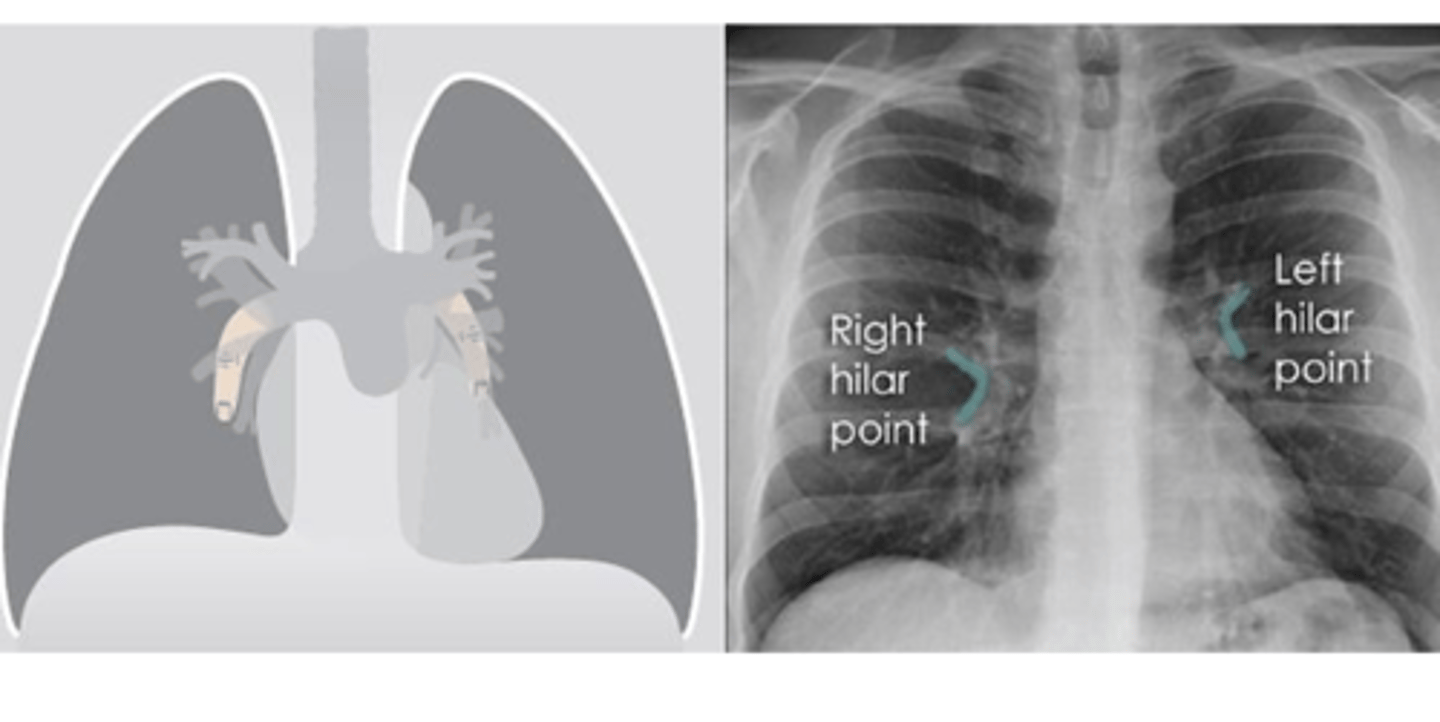

What do the Hilar structures consist of? Is the L or R positioned higher? Why is it important to ID this structure?

•The hilar consist of the main pulmonary vasculature and the major bronchi. (wedge shaped area on central portion of each lung)

•Each hilar also has a collection of lymph nodes which aren’t usually visible in healthy individuals.

•The left hilum is often positioned slightly higher than the right, but there is a wide degree of variability between individuals.

•The hilar are usually the same size, so asymmetry should raise suspicion of pathology.

What is the significance of the hilar point?

⚬where the descending pulmonary artery intersects the superior pulmonary vein.

⚬When this is lost, consider the possibility of a lesion here (e.g. lung tumour or enlarged lymph nodes).

<p>⚬where the descending pulmonary artery intersects the superior pulmonary vein.</p><p>⚬When this is lost, consider the possibility of a lesion here (e.g. lung tumour or enlarged lymph nodes).</p>